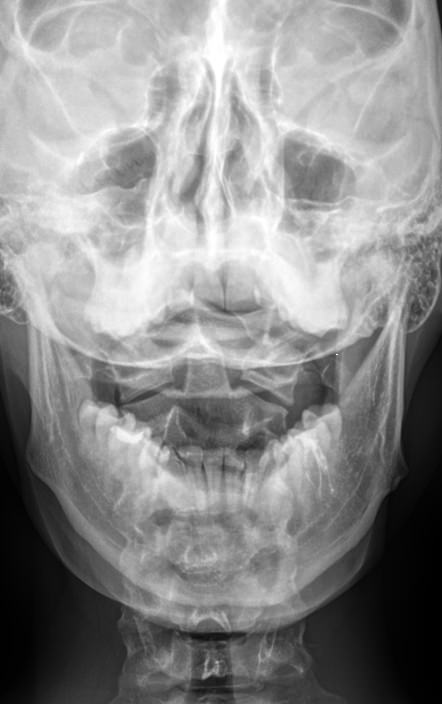

Рентгенография ― первое исследование, которое назначают при подозрении на патологию атланто-аксиального сочленения. На рентгеновском снимке хорошо видны костные образования и их изменения. Самое начало позвоночного столба лучше всего рассматривать в проекции «через открытый рот»: при такой укладке нижняя челюсть и затылочная кость не загораживают исследуемые элементы.

Что покажет рентген шейного отдела позвоночника через открытый рот

• Смещение позвонков друг относительно друга, на сколько и в какую сторону;

• Перелом, если он есть;

• Остеопороз тел позвонков;

• Симметричность и равномерность суставных щелей, костные разрастания;

• Равномерность межпозвоночных пространств.